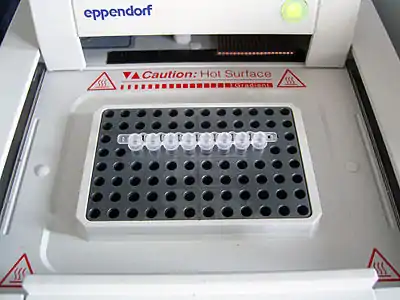

COVID-19-testning kan identificere SARS-CoV-2-virussen og inkluderer metoder, der både påviser tilstedeværelsen af selve virussen (RT-PCR[note 1]) og metoder, der påviser antistoffer dannet som reaktion på infektion.

- Vedr. RT-PCR : "Reverse transcription polymerase chain reaction", polymerasekædereaktion, den kædereaktion der kan opformere genetisk arvemateriale, DNA eller RNA.

- Om "PCR (Polymerase Chain Reaction)" Arkiveret 25. juni 2020 hos Wayback Machine fra Diagnostik.dtu.dk